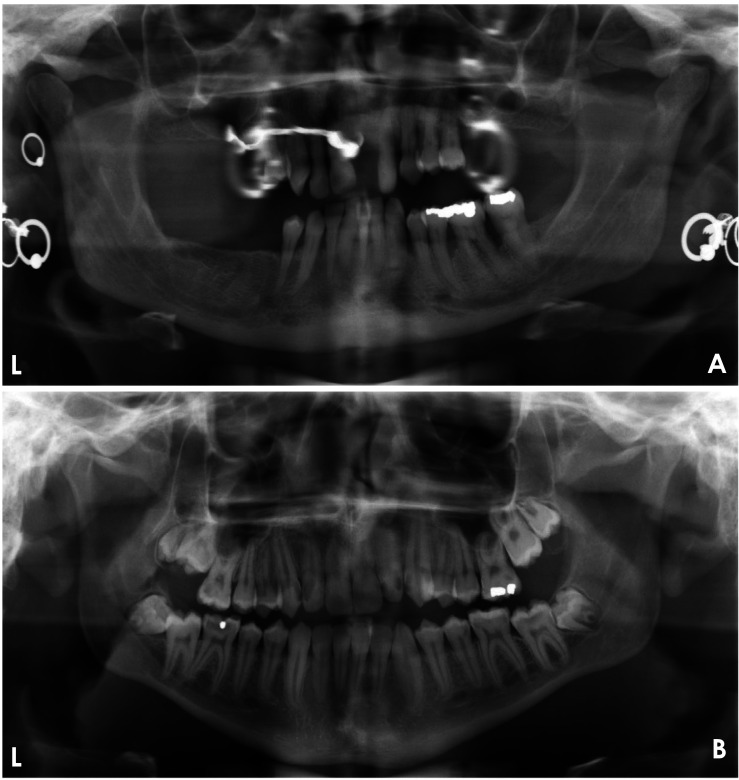

Materials and methods: This study aimed to develop a deep learning (DL)-based model for evaluating the quality of dental panoramic radiographs. A dataset of 1,000 panoramic images, collected from 2018 to 2023, was assessed by 2 trained dentists using predefined grading criteria for contrast/density, artifact presence, coverage area, patient positioning, and overall quality. These expert-annotated scores were used as the ground truth to train and validate 5 YOLOv8 classification models, each targeting a specific quality criterion. The models' performance was evaluated on a separate test set using performance metrics.